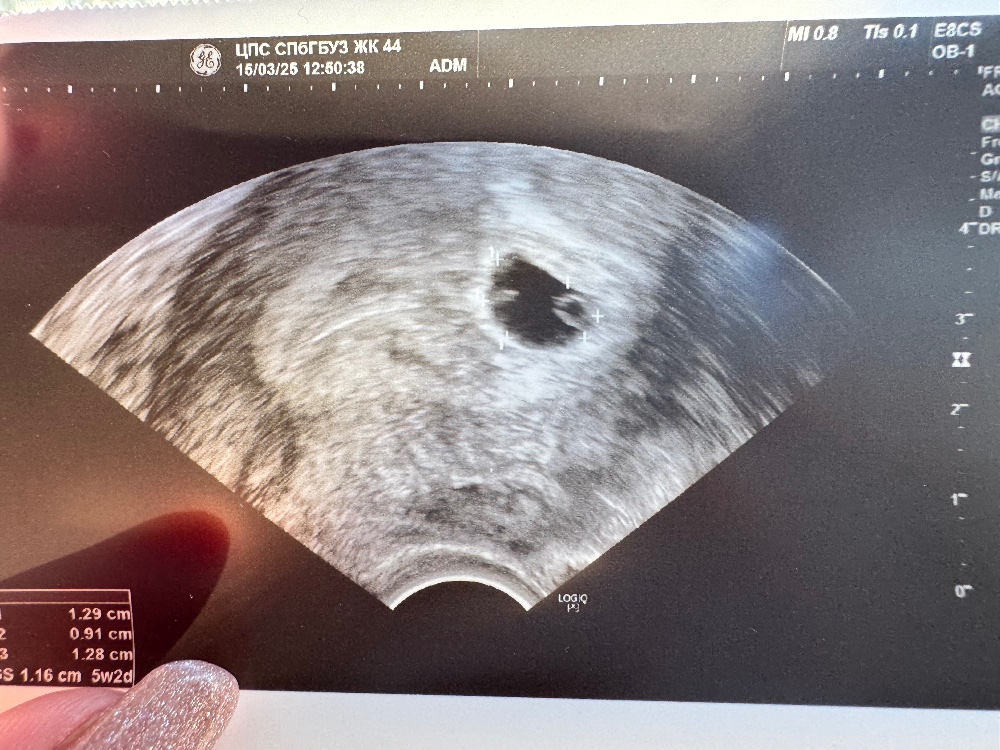

Первое узи прошли )21 дпп, все хорошо